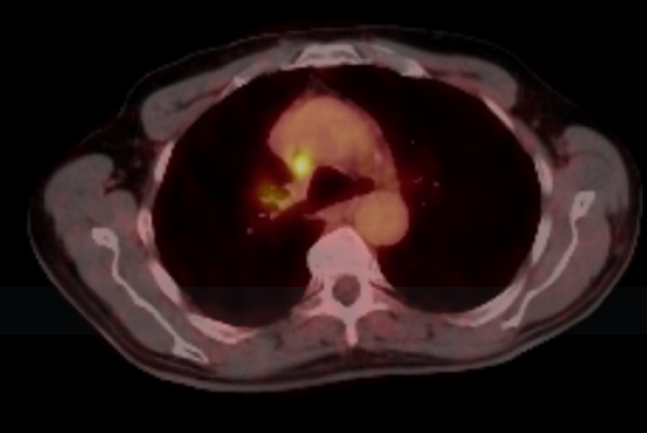

Asymptomatic Testicular Carcinoma Presenting with Metastatic Pulmonary Symptoms: Case Based Review

Cuneyt Tetikkurt, Başak Toksöz and Bilun Gemicioğlu. 12(3): 30-36.